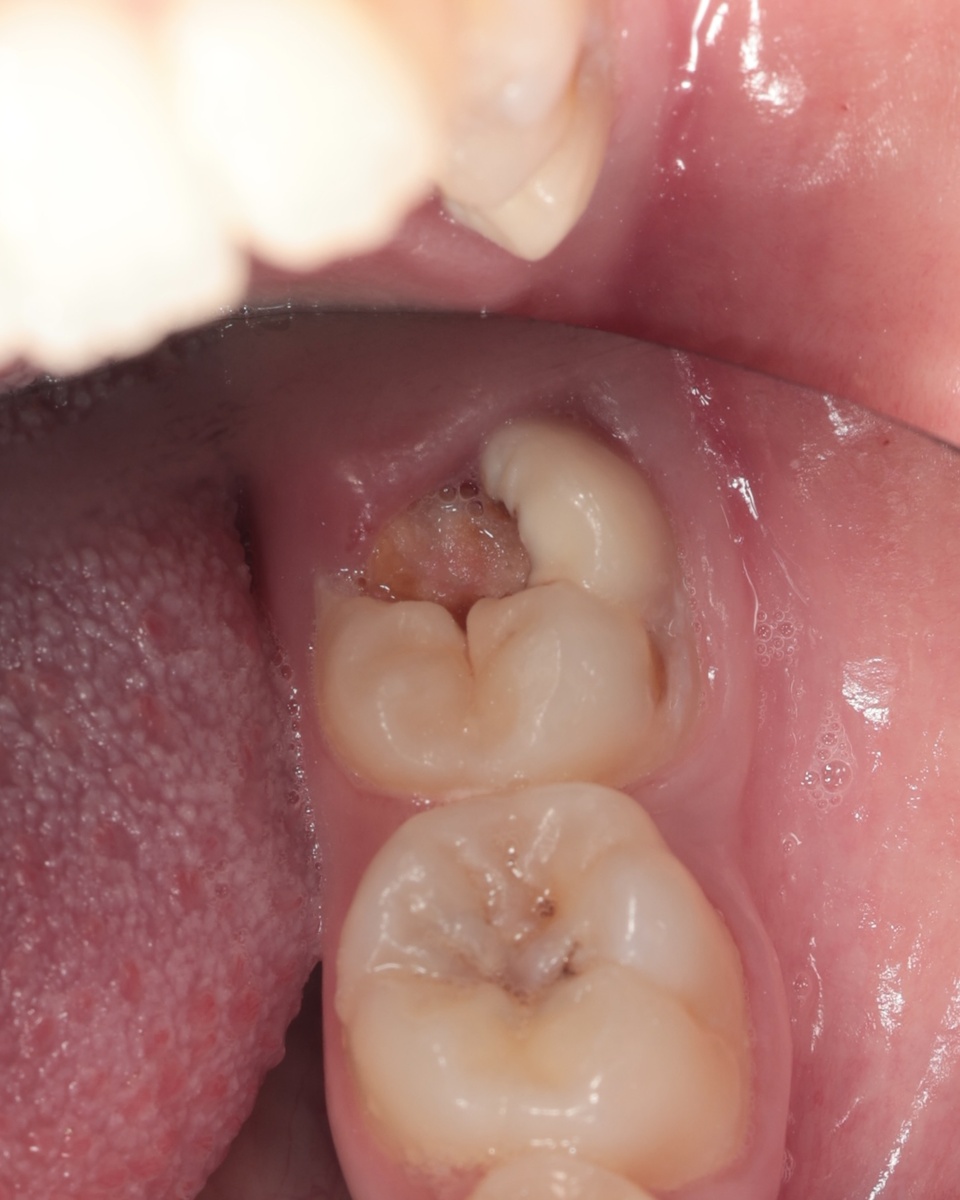

Самым срочным оказался 3.7 зуб - нижняя семёрка слева. На него и обратили внимание в первую очередь:

Фото до лечения

На момент консультации зуб выглядел почти целым. Никаких жалоб - ни боли, ни реакции на горячее, ни ночных приступов. Единственное, что заметила сама пациентка к моменту лечения - небольшой скол стенки. Вот и всё.

Но снимок говорил другое - кариес был огромным.

Десна сильно наросла и перекрывала зуб, к нему было почти не подобраться. Поставить коффердам на этом этапе физически невозможно, так как нет обзора, нет рабочего пространства. Поэтому черновое препарирование (удаление основного массива кариозных тканей) проводилось без изоляции.